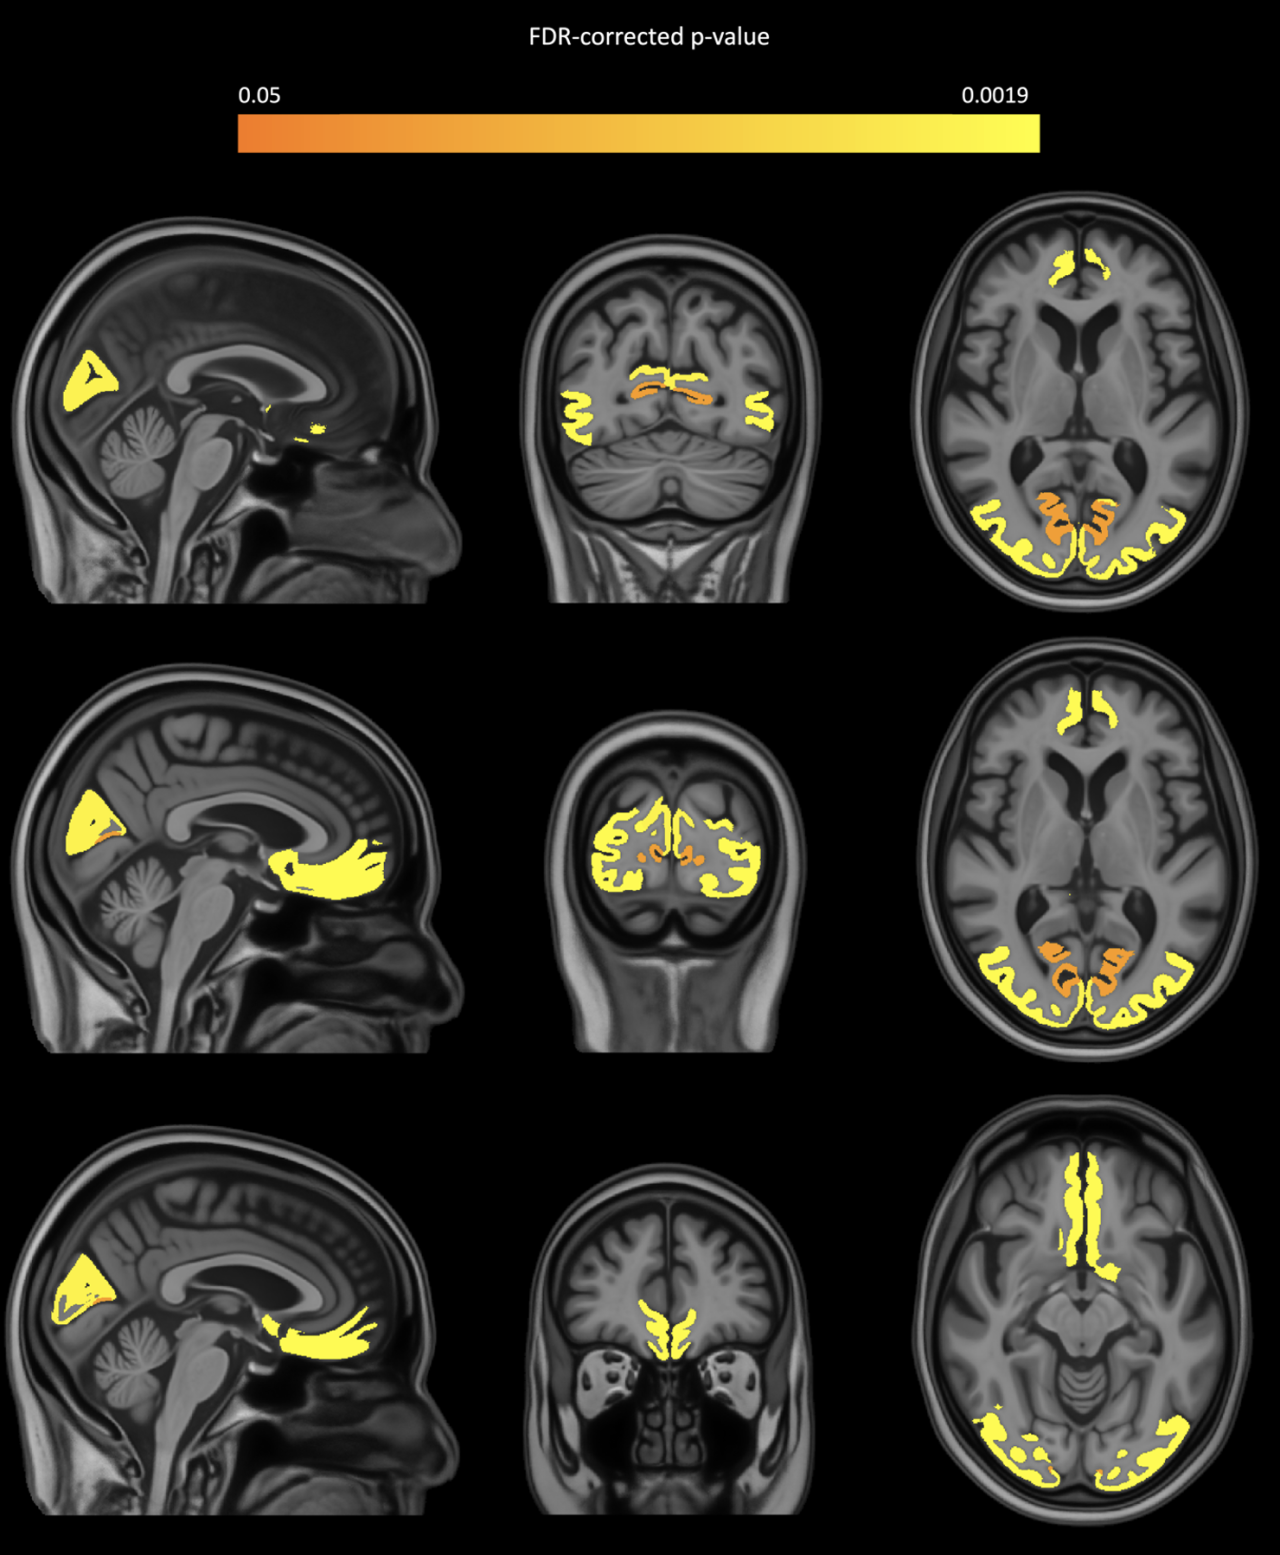

该研究调查了社区老年人脑小动脉硬化与区域灰质体积之间的关系。研究者结合了体外MRI和精细的神经病理学评估,对来自四个老化纵向临床病理学队列研究的82名老年成人的大脑半球进行了分析。研究结果显示,脑小动脉硬化与包括内侧额叶、顶叶和枕叶在内的多个灰质区域体积较低相关,且这种关联独立于其他神经病理学效应。这些发现有助于深入理解脑小动脉硬化在神经退行性疾病中的潜在作用。

矢状面、冠状面和轴位图像显示了灰质区域的体积减少,这些区域的动脉病硬化更为严重,这些图像叠加在MIITRA图谱上。颜色标尺代表经过FDR(假发现率)校正的p值。